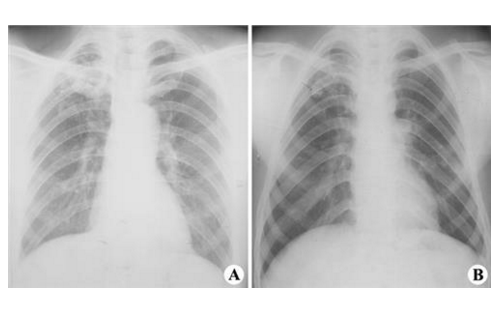

結核菌素試驗、X線檢查

肺結核圖片